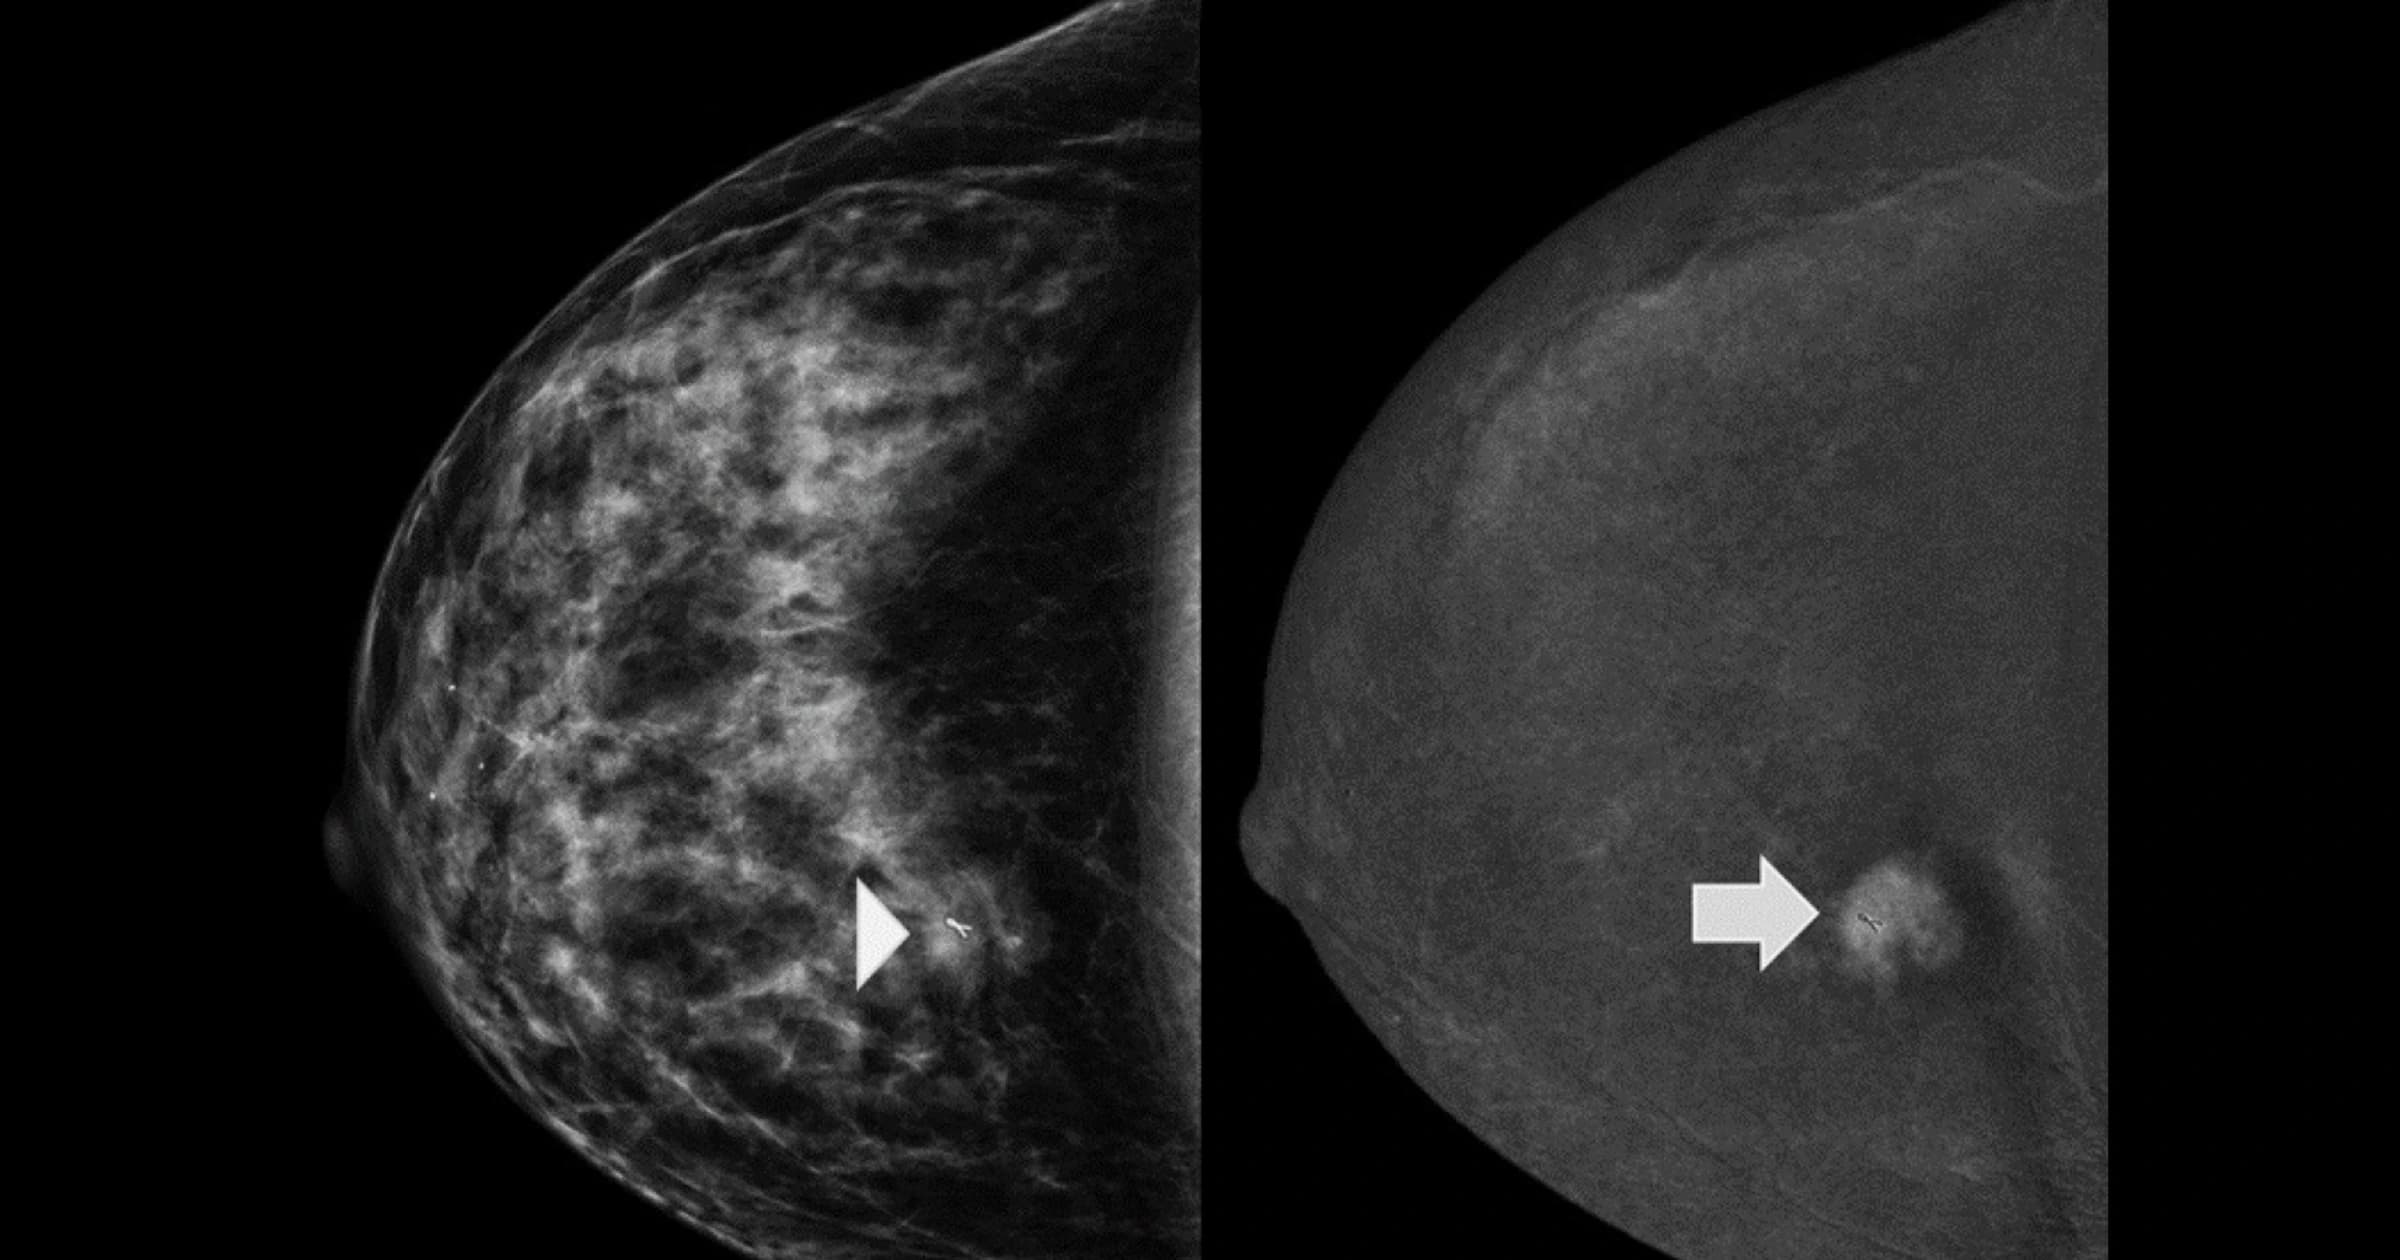

On the left is a standard 2D mammogram – the breast tissue appears dense, and the cancer is barely visible (indicated by the arrowhead). On the right is a contrast-enhanced mammogram of the same breast, which clearly outlines the cancer's size and shape and confirms it's the only tumor present (arrow).

Photo Courtesy of MD Anderson